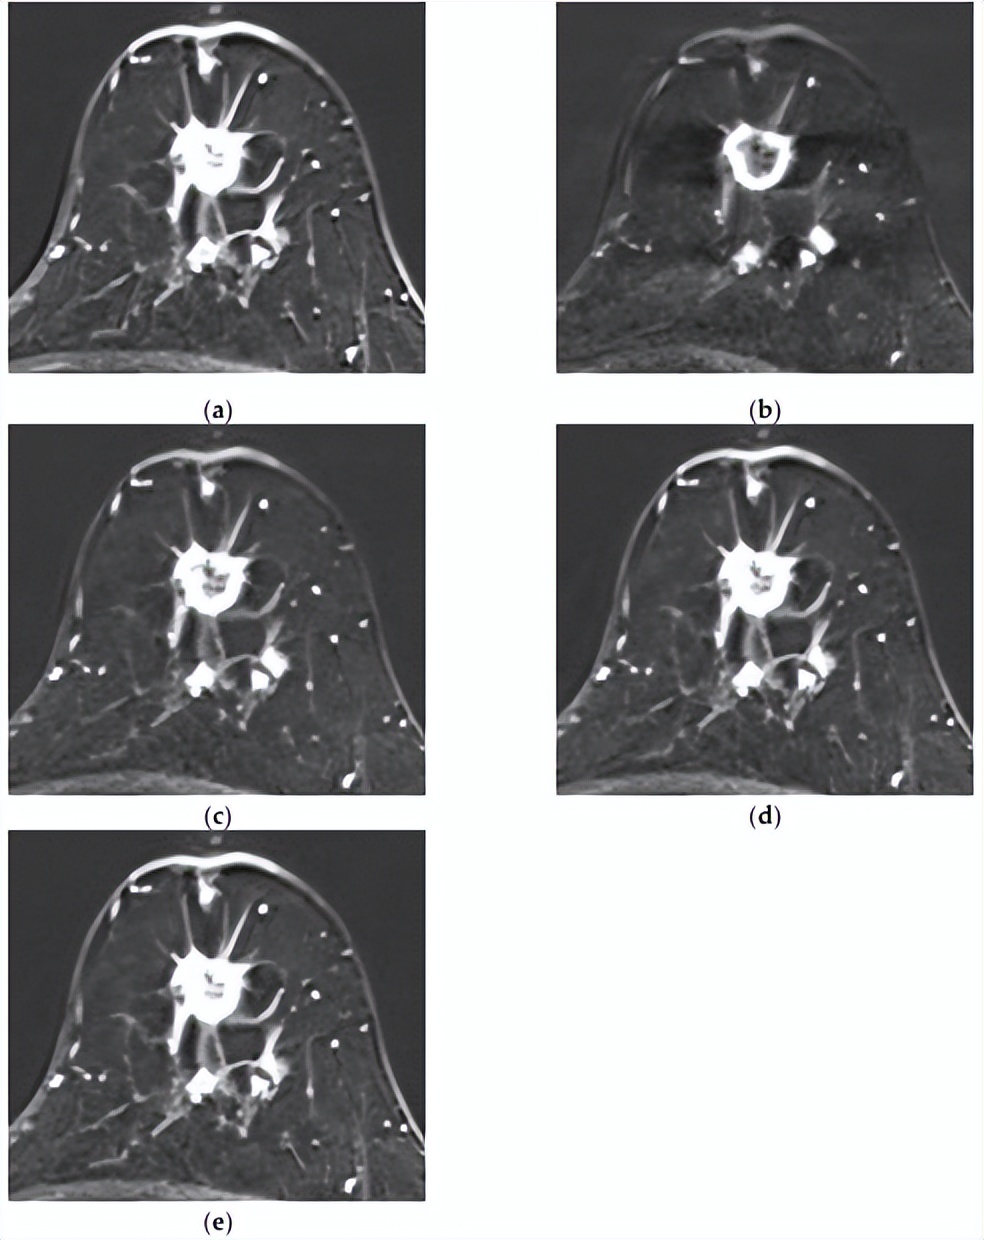

[组合模型正确预测了复发,而MRI模型则没有。一名73岁的女性,乳房几乎完全脂肪化,BPE极小。注射造影剂后(a)1分钟、(b)2分钟、(c)3分钟、(d)4分钟和(e)5分钟的轴向增强T1加权MR图像显示,右下内象限有一个1.4×1.7厘米的不规则形状、边缘不规则肿块,内部增强不均匀。病灶表现出快速的初始增强,随后呈现平台期动力学曲线模式。未发现腋窝淋巴结转移。MRI深度学习模型无法预测该复发病例,但整合临床病理学和MRI特征的组合模型可以正确预测。]

△HER2低表达乳腺癌复发的代表性病例

[MRI和组合模型均正确预测了复发。一名50岁女性,具有不均匀致密的纤维腺体组织和中度背景实质强化。注射对比剂后(a)1分钟、(b)2分钟、(c)3分钟、(d)4分钟和(e)5分钟的轴向增强T1加权MR图像显示,左乳房12点位置有一个1.8×1.6厘米的不规则形状、边缘有毛刺、边缘增强的肿块。在主要病变后方可见另一个8毫米增强肿块,侧面还有另外两个8毫米增强肿块,它们似乎相互连接。虽然图像中未显示,但上内象限存在另一个增强病变,证实了多中心疾病。两种模型均成功预测了该复发病例。]